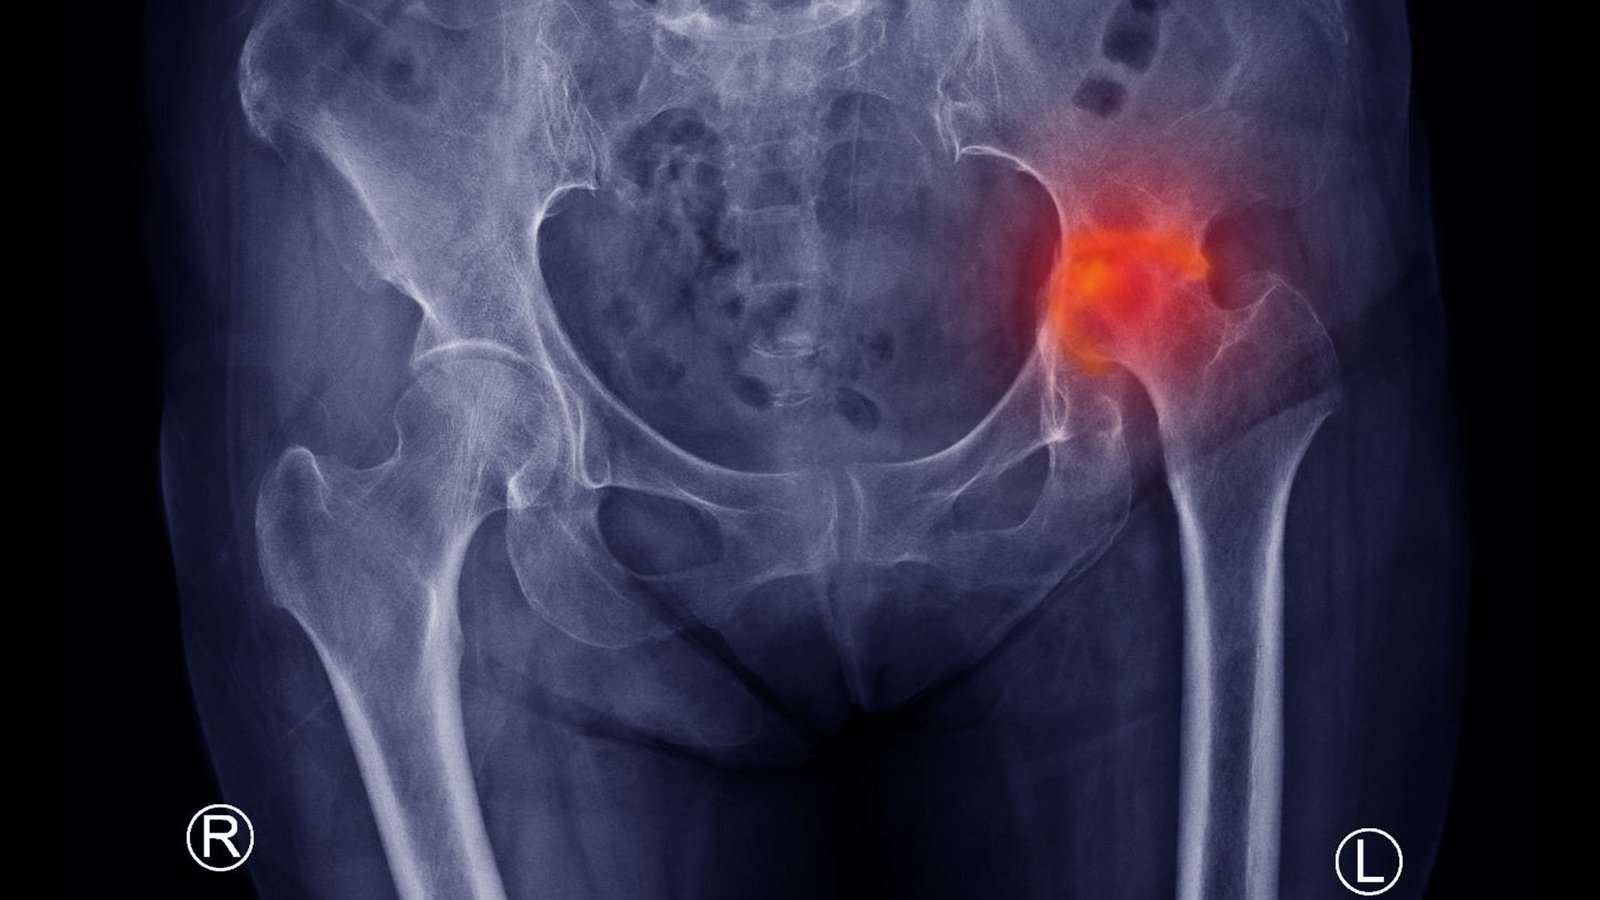

X-ray

Shows changes in bone shape and joint surface, especially in later stages.

Stages of AVN

AVN is classified into stages:

- Early stage – Blood supply reduced, but bone shape is maintained

- Collapse stage – Bone begins to cave in

- Advanced stage – Joint surface damaged; secondary arthritis develops